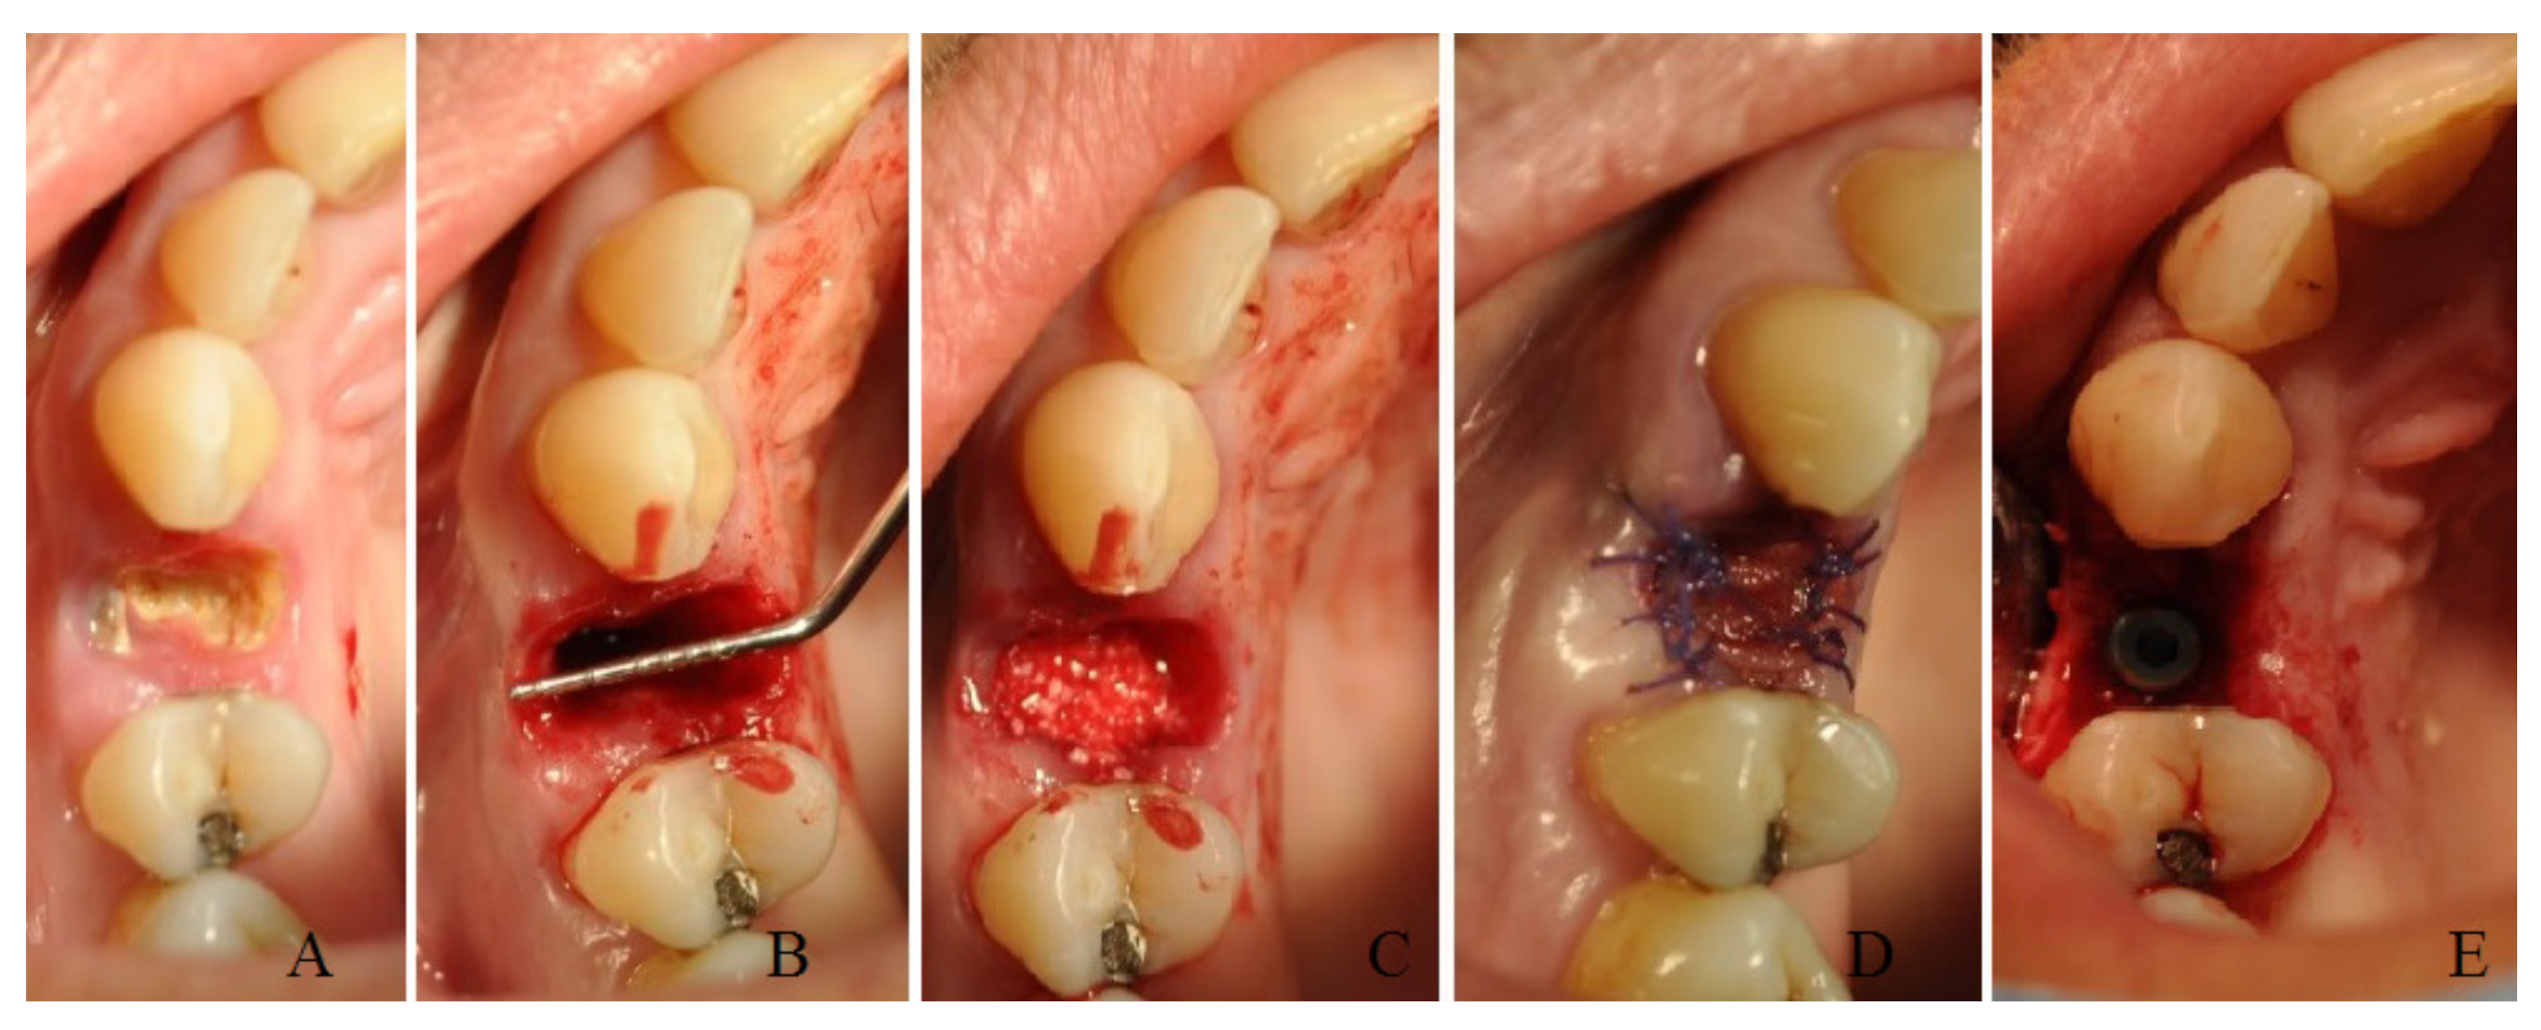

A total of 11 patients (group A) after tooth extraction received deproteinized bovine bone (Bio-oss, Geistlich Pharma Italy, Thiene, Italy) inside the alveolar socket covered with a resorbable collagen matrix (hemocollagene, septodont, Mataro, Spain) with a diameter of 8 mm sutured at the soft tissue with resorbable stitches (Figure 1).

Figure 1. A case of socket preservation performed with a sponge of deproteinized bovine bone inside the alveolar socket covered with a resorbable collagen matrix and the insertion of a dental implant after four months: preoperative image (A); image after the extraction (B); image after the filling with deproteinized bovine bone (C); image after placement of collagen matrix and suture (D); image after recovery at time of implant surgery (E).